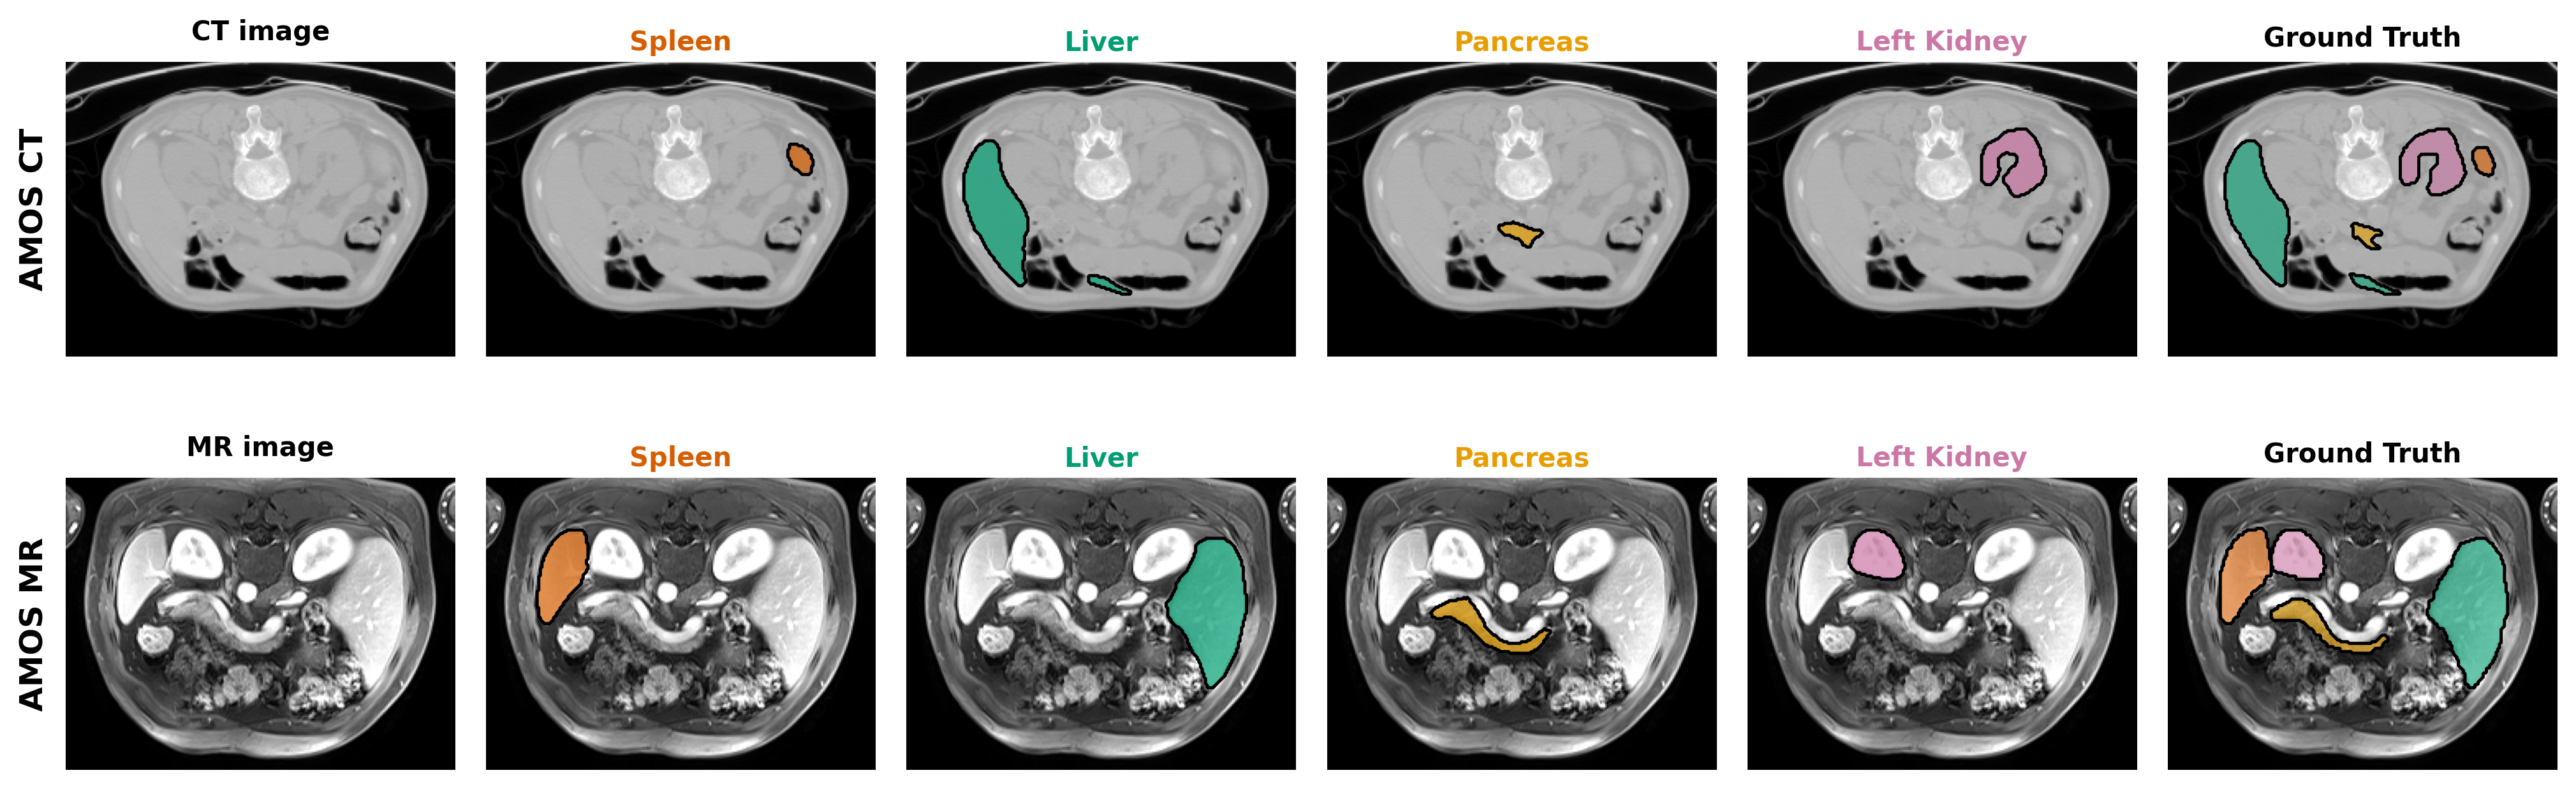

Refer to caption

Figure 3: Controllable, dual prompt-driven organ segmentation across datasets. Each row shows one CT dataset (BCV abdomen; STRUCTSEG OAR thorax). Columns: CT image, four prompted predictions, and Ground Truth. Inference uses two text prompts: (T1) a modality/region context, fixed per row (“A computed tomography of abdomen” for BCV; “A computed tomography of thorax” for STRUCTSEG OAR); and (T2) a target-organ prompt that is changed per column (“A computed tomography of spleen/liver/pancreas/left kidney” in BCV; “left lung/right lung/heart/spinal cord” in OAR). Holding T1 constant and switching only T2 deterministically switches the predicted structure on the same slice, demonstrating fine-grained text control without altering the image or model weights. Colored title fonts indicate the mask color for each organ; “CT image” and “Ground Truth” provide qualitative reference.

The qualitative results in Figure 3 and Figure 4 visually validate the effectiveness and flexibility of our dual-prompt architecture. They specifically showcase the model’s precise, on-demand target control and its robust adaptability across different imaging modalities and organs.

Figure 3 illustrates the fine-grained control offered by our target-specific prompt, T2T_{2}. For the same input CT slice, simply altering the target organ in the prompt - from “spleen” to “liver” to “pancreas”, deterministically switches the output model to accurately segment only the requested structure. This result highlights the model’s ability to disentangle and isolate specific anatomical targets based purely on textual instruction, without any change to the input image or model weights.